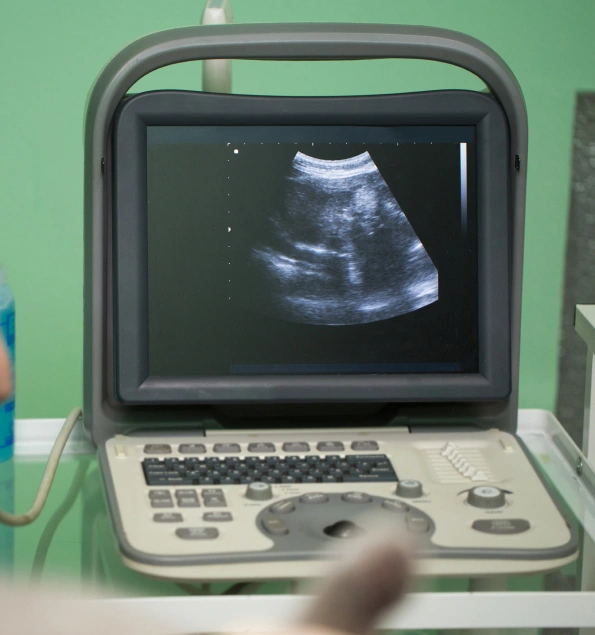

Our veterinary clinic, Independence Veterinary Clinic, offers advanced cat ultrasound in Charlotte, a non-invasive test that helps detect a range of health problems your cat may be facing. Ultrasound is a valuable diagnostic tool that helps our staff scan and visualize internal organs and soft tissues, enabling an accurate assessment of their health.

- Issues with Internal Organs: Ultrasound images help detect abnormalities in major internal organs, such as the heart, liver, kidneys, and spleen, as soon as they develop.

- Scanning for Pregnancy in Cats: If your cat is pregnant, she can be scanned to confirm her pregnancy and assess her health and her kittens' health.

- Growths & Tumors Detection: Helps determine the size, location, and malignancy of tumors and growths.

- Assessing Internal Injuries: In case of trauma to your cat, an ultrasound test is employed as an apparatus for diagnosing an internal injury of the cat.

- Evaluating Soft Tissue: Ultrasound is readily used to evaluate inflammation, cysts, or fluid accumulation.